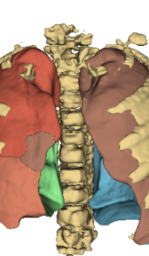

Fig. 2 presents a visual comparison of lung coronal sections from different models. The model using L1 loss results in blurred images, with particularly poor bone reconstruction. In contrast, the MedicalNet-based model produces sharper images but introduces artifacts in anatomical areas. Models based on AFP loss offer visually appealing results, with well-reconstructed anatomical bones and lung tissue. Additionally, only NaviAirway and HAL methods provide detailed bronchial reconstruction, as highlighted in the zoomed-in section.

Table 3 and Fig. 5 present a comparison of the models on the reconstruction of lung anatomical regions using the TotalSegmentator (TotalSeg) pipeline with Dice score and NSD. The model trained with the AFP loss using TotalSeg’s embeddings provide the best performances. For example, when reconstructing bones, this model achieves a NSD of 0.629, outperforming the L1 loss model (NSD: 0.493) as well as perceptual loss (NSD: 0.499). A combination of AFP loss using NaviAirway and HAL’s embeddings also delivers positive results, whereas other models exhibit notably poorer reconstructions especially in the bones.